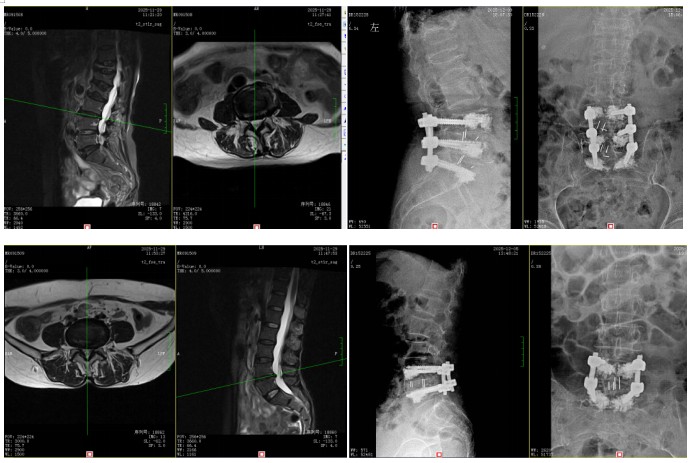

輾轉(zhuǎn)多地求醫(yī),她們了解到衡陽市中心醫(yī)院脊柱外科錢軍博士在治療腰椎間盤突出方面經(jīng)驗豐富,母女倆便一同找上門來。錢軍博士詳細(xì)詢問了病史,并為她們進(jìn)行了系統(tǒng)的體格檢查和影像學(xué)評估。結(jié)果顯示,唐奶奶是腰4/5、腰5/骶1節(jié)段椎間盤突出,嚴(yán)重壓迫椎管內(nèi)神經(jīng)及右側(cè)神經(jīng)根受壓;王女士則是腰5/骶1節(jié)段椎間盤突出,左側(cè)隱窩狹窄,神經(jīng)根受壓明顯。兩人均符合手術(shù)指征。

“腰椎間盤突出壓迫神經(jīng)根,就像石頭壓住了水管,不通則痛,還會導(dǎo)致下游‘田地’(腿部肌肉)缺血‘營養(yǎng)不良’,出現(xiàn)麻木、乏力?!卞X軍博士用形象的比喻向母女倆解釋了病情,“當(dāng)保守治療無法搬開‘石頭’時,就需要手術(shù)來徹底減壓?!笨紤]到兩位患者的年齡、身體狀況和病變特點,錢軍博士團(tuán)隊進(jìn)行了深入的術(shù)前討論,為她們分別制定了精準(zhǔn)的手術(shù)方案。手術(shù)的核心目標(biāo)是在充分解除神經(jīng)壓迫的同時,最大程度減少創(chuàng)傷,保護(hù)脊柱穩(wěn)定性。通過精密的操作,成功摘除了壓迫神經(jīng)的突出髓核組織,解除了神經(jīng)根的“枷鎖”。